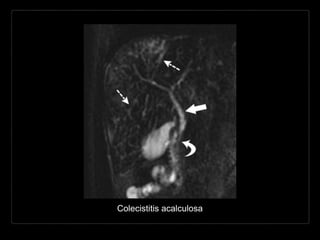

Colecistitis acalculosa

Hallazgos por RM

• T1: dilatación hipointensa de los conductos biliares

• T2: dilatación hiperintensa de los conductos biliares y

el colédoco

• engrosamiento de la pared de la vesícula

• T1 + C: … + cambios inflamatorios pericolecísticos

• CPRM: dilatación hiperintensa de los conductos

biliares + estenosis intra- y extrahepáticas